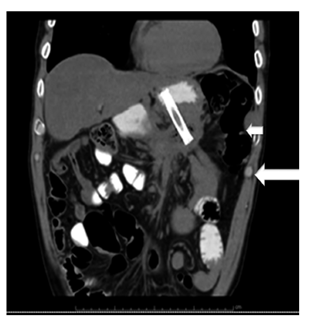

Según los hallazgos ecoendoscópicos, el 80% de las lesiones correspondía a pseudoquiste pancreático y el 20% a colección líquida con necrosis pancreática amurallada (walled-off). No hubo muertes asociadas con el procedimiento. Se realizó control tomográfico abdominal 6 semanas después del procedimiento (Figura 3) en el que se evidenció una resolución completa del pseudoquiste en el 90% de los casos sin complicaciones. Todos los pacientes con cistogastrostomía resolvieron completamente la lesión, la paciente a quien se realizó drenaje por aspiración presentó recidiva del pseudoquiste a nivel del cuerpo del páncreas a las 4 semanas.